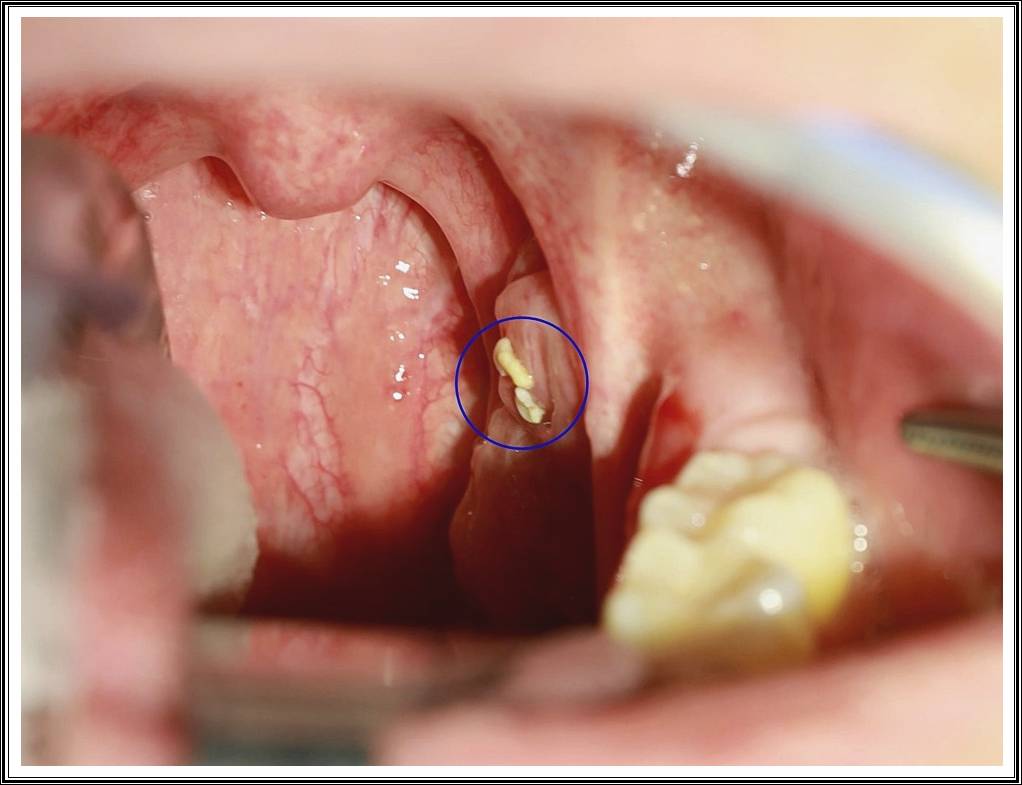

편도결석(tonsillolith)은 편도선의 틈새에 음식물 찌꺼기, 점액, 죽은 세포 등이 쌓여 굳어진 덩어리입니다.

흰색 또는 노란빛을 띠며, 크기는 좁쌀 정도에서 콩알만 한 크기까지 다양합니다.

편도 표면에 작은 흰색 알갱이나 덩어리가 보이면 결석일 가능성이 큽니다. - 혀압자나 면봉 사용

편도 부위를 살짝 눌렀을 때 흰색 조각이 나오는지 확인합니다.

단, 무리하게 누르면 통증·출혈이 생길 수 있으니 주의하세요.